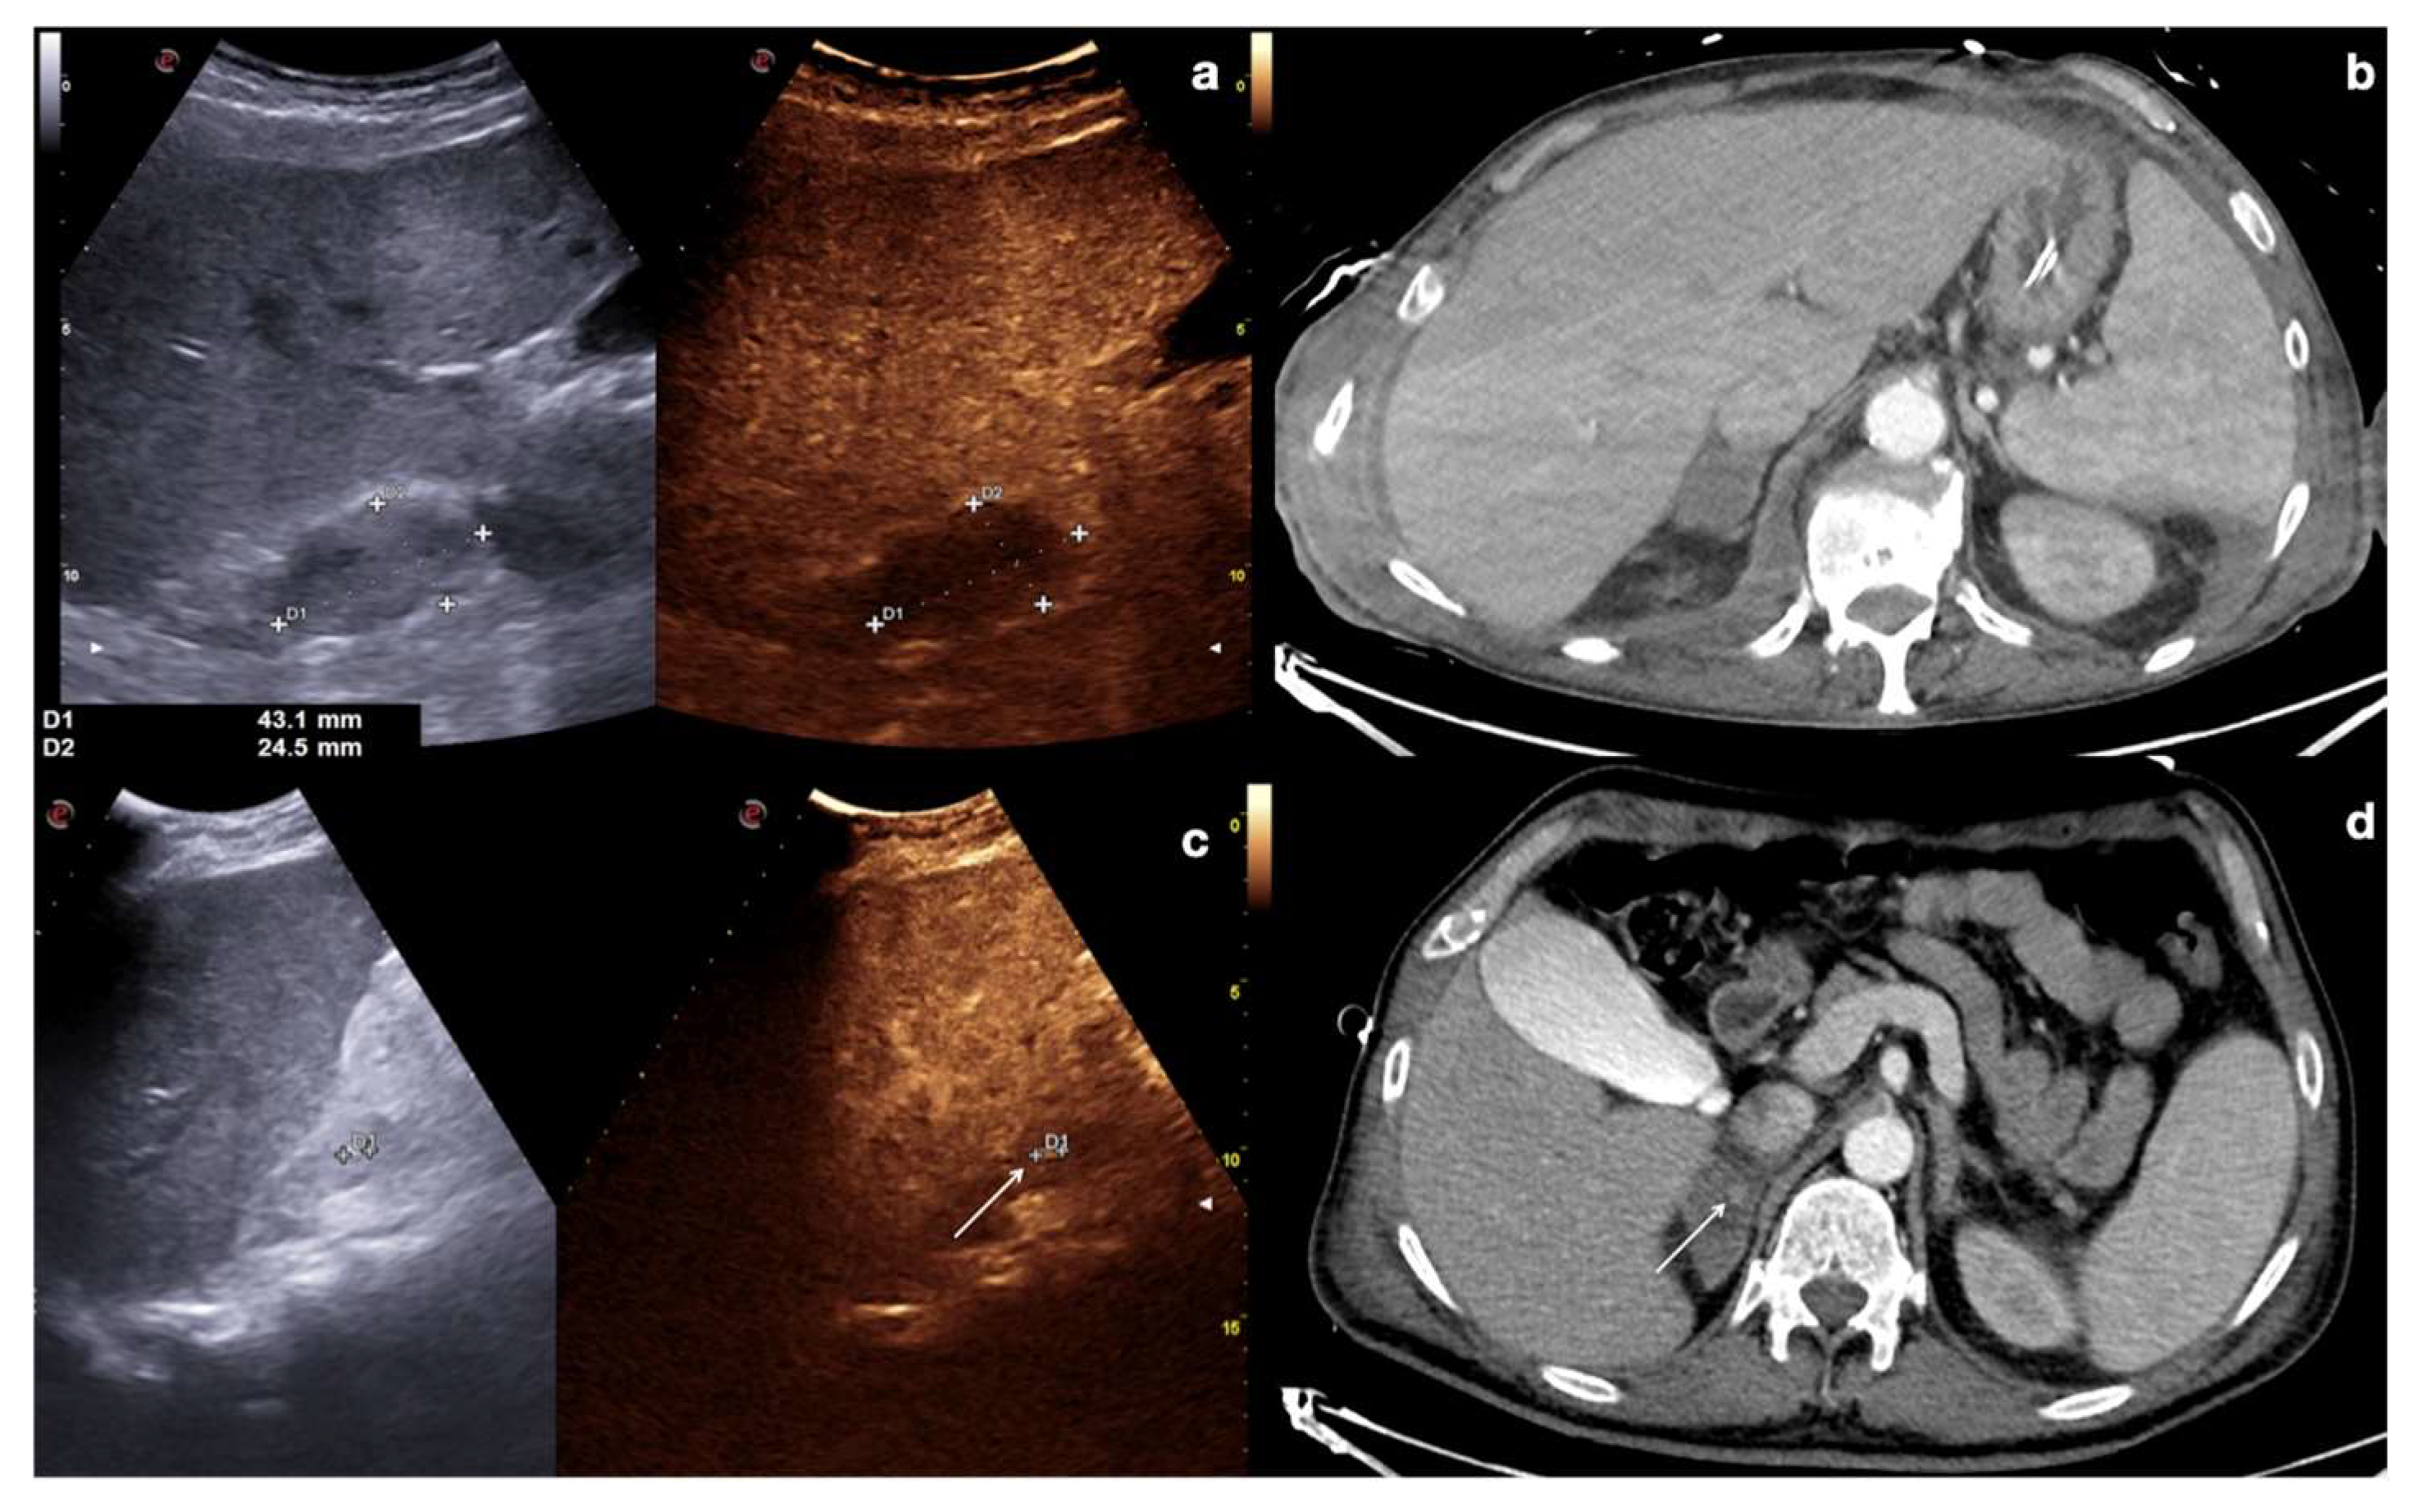

Lacerations: these findings are identifiable as irregular linear or branched non-enhancing bands, frequently perpendicular to the organ capsule, and can be associated with capsular discontinuity. Lacerations can be classified as superficial (≤3 cm in depth) or deep (>3 cm in depth) (Figure 12, Figure 13, Figure 14, Figure 15 and Figure 16) [13].

Figure 12.

Example of CEUS imaging of low grade (first column) and high grade (second column) injuries in the liver (a) and spleen (b) after moderate energy blunt trauma. Orange lines indicate parenchymal lacerations/haematomas.

Figure 13.

CT (a) and follow-up CEUS (b,c) of the right kidney in a 16−year-old patient with blunt trauma. At the admission, CT detected a kidney laceration reaching the organ capsule (a, arrow). CEUS was performed ten days after trauma (b,c), showing minimal healing of the laceration without vascular injuries. Adopted from ref. [30], 2021, Iacobellis, F.; et al.

Figure 14.

Admission CT (a,b) and follow-up CEUS (c–o) of a 35−year-old blunt trauma patient with multiple hepatic lacerations. Follow-up CEUS was performed 3 days (c–e), 11 days (f–i), and 20 days (l–o) after the admission CT. Note at CEUS the progressive enhancement of the liver parenchyma in the different phases. The parenchymal lacerations appear as non-enhancing bands (c, orange line), some of them reaching the liver capsule (pink line) (e,i). In the follow-up, it is important to look for possible vascular injuries (absent in this case) in the early arterial phase (f,l). Parenchymal lacerations appear progressively better demarcated, and more hypoechoic. Adopted from ref. [30], 2021, Iacobellis, F.; et al.